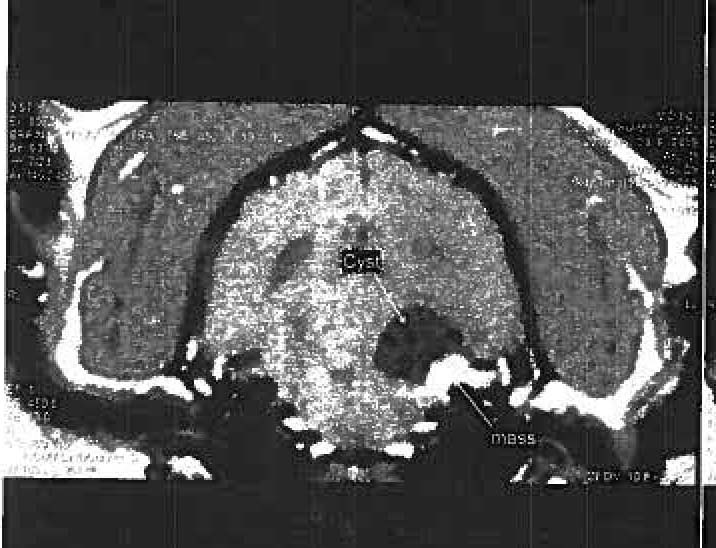

This time the MRI, November 9th, 2009, revealed a brain tumor which is thought to be a meningioma or a trigeminal nerve tumor. It is not small, and there is a fluid filled cyst adjacent to it three times the size of the tumor. This was causing severe pressure in her brain and resulting in dizziness, loss of balance, etc. It means that she has a few months left absent treatment. She is seven next week. A rather poor copy of an image from the scan is posted above.